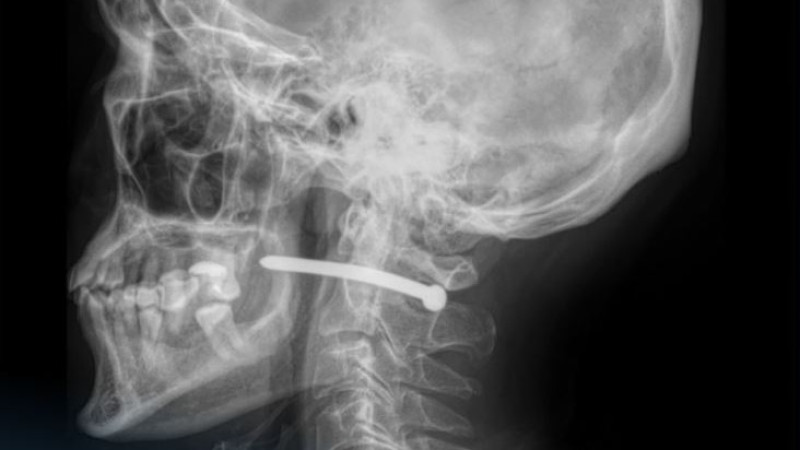

Врачи рассказали, что рентген показал, что гвоздь прошёл рядом с шейным отделом позвоночника, что могло привести к серьезным травмам. К счастью, жизненно важные структуры не были задеты. Медики отметили высокую опасность травм в области шеи, поскольку рядом проходят крупные сосуды, нервы и дыхательные пути. Даже небольшие повреждения могут иметь серьезные последствия.

Челюстно-лицевые хирурги больницы провели операцию по удалению гвоздя, обработали рану и наложили швы. После инцидента врачи вновь подчеркнули важность соблюдения техники безопасности при работе с инструментами.